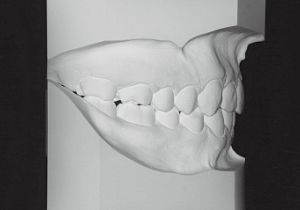

2 After Treatment 6-24-’95

Class II deep bite in mixed dentition. A significantly large overjet and a spaced arch are observed. The cephalometric X-ray shows that the anteroposterior displacement of the maxilla and mandible is not particularly large (ANB 5°), but the nasal floor is elevated anteriorly, providing evidence supporting a history of thumb sucking. The skeletal form shows a relatively slight mandibular body deficiency, but the mandibular ramus is adequately sized and appears likely to develop sufficiently. The use of headgear was planned to suppress maxillary anterior growth and achieve relative mandibular advancement. Treatment was performed without extraction, assuming continuity until the permanent dentition stage.

3 Initial Visit 9-3-’91

4 After Treatment 6-24-’95 3 years and 7 months after starting treatment